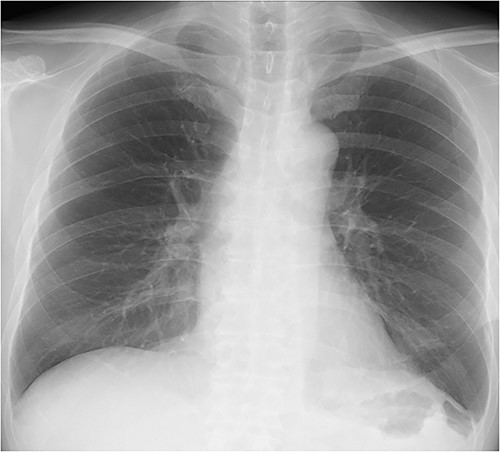

The patient’s postoperative course was uneventful. Oral intake was started the day after surgery, and the patient was discharged home on postoperative day 12. There was no sign of complication or relapse of hernia after surgery (Fig. 4).